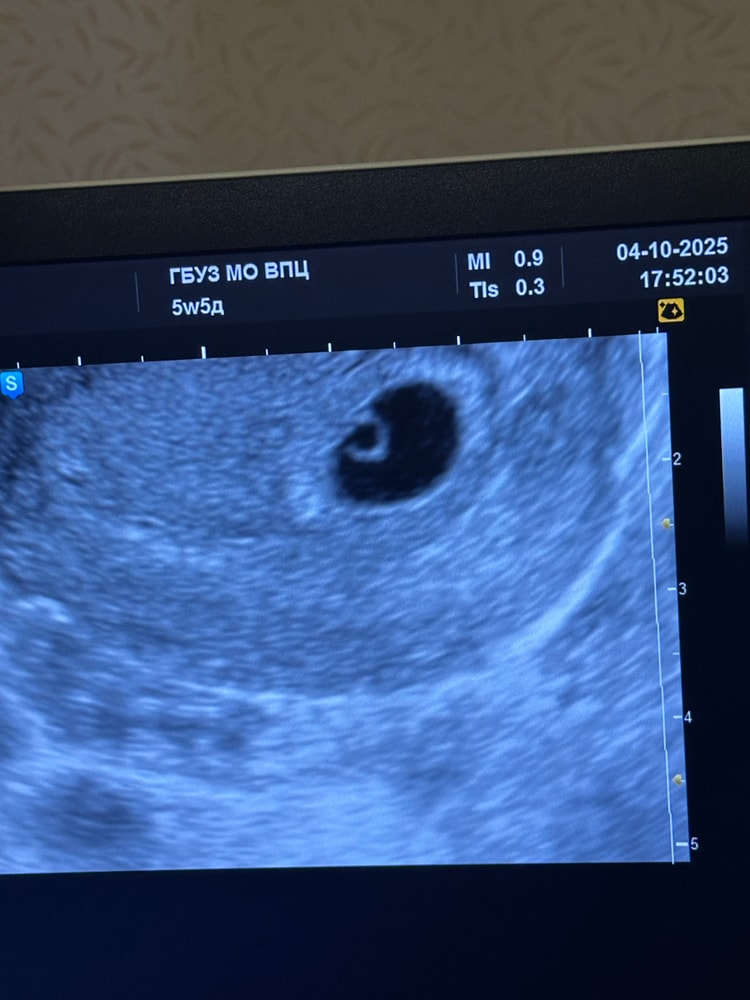

Делают УЗИ:

В полости матки визуализируется плод.яйцо внутр.диаметр 12,0 мм и эмбрион КТР 1,6 мм . Жёлточный мешок + 3,5 мм, СБ - .

Кольцевидный хорион с участками отслойки по передней стенке 5*3 MM

Тонус миометрия в норме

Шейка матки: длина 42 мм. Цервикальный канал: сомкнут, на всем протяжении.

Заключение: Беременность малого срока

Отслойка хориона с формированием ретрохориальной гематомы.